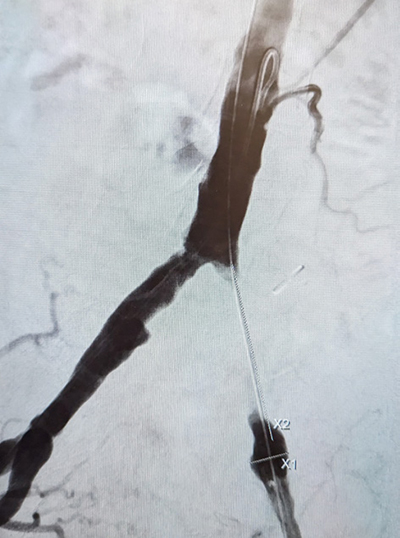

Particularly interventions that require a large dissection or insertion of synthetic grafts benefit from a hybrid approach. Bypass surgery, where the proximal intervention’s patency is dependent on the distal runoff or iliac PTA and common femoral endarterectomy with or without bypass, should be performed either simultaneously or soon thereafter to prevent thrombosis of the proximally treated artery or the bypass graft. Many centers have implemented the practice of completion angiography for all peripheral bypass surgeries to verify the patency of the inflow, outflow and the graft to prevent early occlusions of the graft. Upon identification of a technical defect immediate treatment can be performed by the operating physician at the index procedure, such as revision of an anastomosis, excision of a retained valve or ballooning or stenting of a residual stenosis, dissection or tandem lesion.

Common femoral endarterectomy, combined with open iliac artery transluminal angioplasty and stent as well as Iinfrainguinal bypasses distal to either an iliac or superficial femoral artery (SFA) lesion are ideal candidates for a combined approach.

Particularly peripheral arterial disease has seen a rise in hybrid procedures. Peripheral bypass surgery has become a last option nowadays. In most scenarios vascular surgeons and interventionalists chose an endovascular-first approach with peripheral arterial lesions. Several studies such as the BASIL trial have supported this approach, albeit with some reservations for long occlusions. Physicians are pushing the envelope to treat long lesions now using novel atherectomy devices, which physically remove atheromas and calcium using diamond blades with promising results.